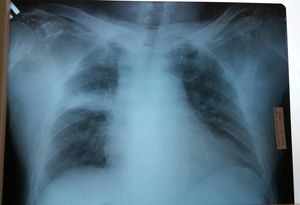

Diagnose it.

Low KV radiograph >> TGA, right middle lobe consolidation ?

Cardiomegaly